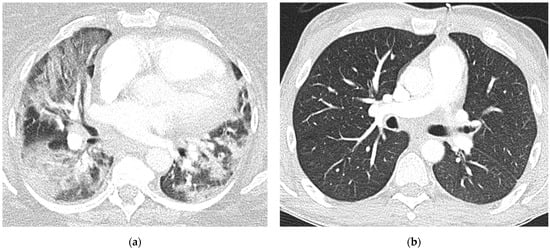

3.2. Qualitative Scoring, Pattern Distribution, Morphology, and Virus Variant

3.3. Semiquantitative Scoring and Virus Variant